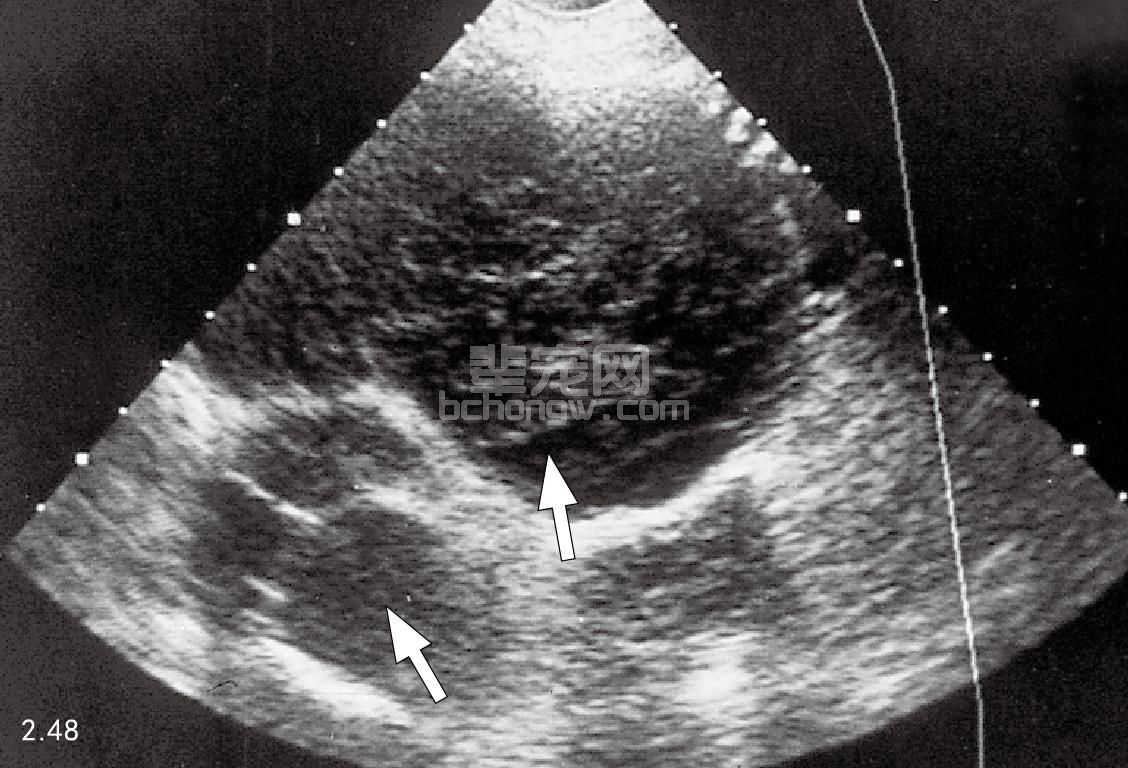

图2.48 患有颅侧胸腔纵隔淋巴瘤的6岁大丹犬的胸部超声波图:小块次回 声肿块(箭头所示)。